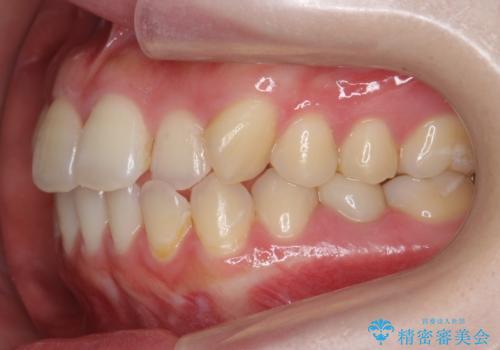

犬歯のねじれ 上の歯が引っ込んでいる

- 前歯の並びを気にして来院。

インビザラインで、上の前歯をやすり掛けして並べました。

途中妊娠、出産を挟み、患者様がアライナーがつけられない時期もあって治療自体は延長しました。